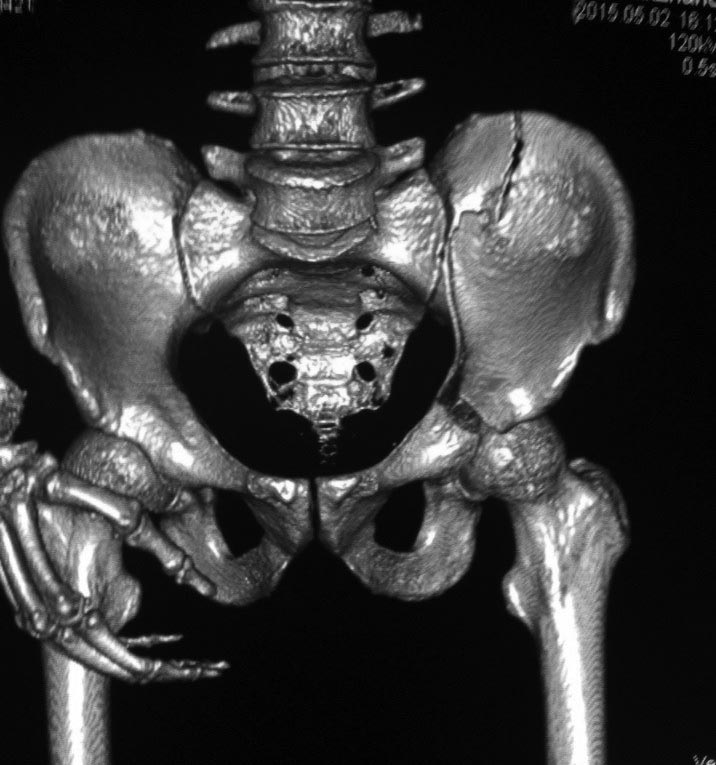

Это высокий перелом передней колонны вертлужной впадины (62A3.2).

Аппарат или гамак тут не сильно нужны, здесь нет нестабильности кольца, задние структуры целы.

Появились новые проекции. Да, это высокий перелом передней колонны левой вертлужной впадины со смещением.

Да, я понимаю, что предпочтительнее всего накостный синтез. Но если сравнивать АВФ с миниинвазивным, то ни тот ни другой не гарантируют 100%й репозиции. Перелом начинается с передней стенки впадины, идет вверх до крыла, а сзади спускаясь, останавливается едва достигнув задней колонны. Да, задняя колонна цела. Есть поперечные срезы КТ (сейчас показать не могу), где это четко видно. Перелом не завершенный. Учитывая этот факт, я и подумал о возможности АВФ. Простите мне мою упрямость)).

Относительно диагноза соглашусь с коллегами повреждение крыла и передней колоны вертлужной впадины ближе к типу В по классификации Летурнеля, хотя не в полной мере ей соответствует. Согласно Матта смещение более 3х мм -показание к открытому остеосинтезу, в данном случае скорее из илиоингвинального доступа или Стоппа. Хотелось бы конечно увидеть остальные срезы и рентгенограммы.

Дискуссия показывает интересные стороны развития тактики лечения переломов вертлужной впадины. Для разработки лечебной тактики сперва надо установить диагноз, и разбор показывает, что не все справляются с такой задачей! Изучение перелома надо начать из стандартных снимков: для переломов костей таза: прямой, inlet и outlet, а для перелома вертлужной впадины - снимки по Judet.

В последнее время, из-за красоты участился показ 3D снимков, хотя надо начать c обычных, и, по необходимости, компьютерная томография с 3D! Без головки бедра 3D покажет общую картину и вовлечение сустава, а более детально только в срезах КТ.

Данная картина показывает очень редкий перелом передней колонны, но перед операцией еще раз надо просмотреть обещанные дополнительные КТ срезы.